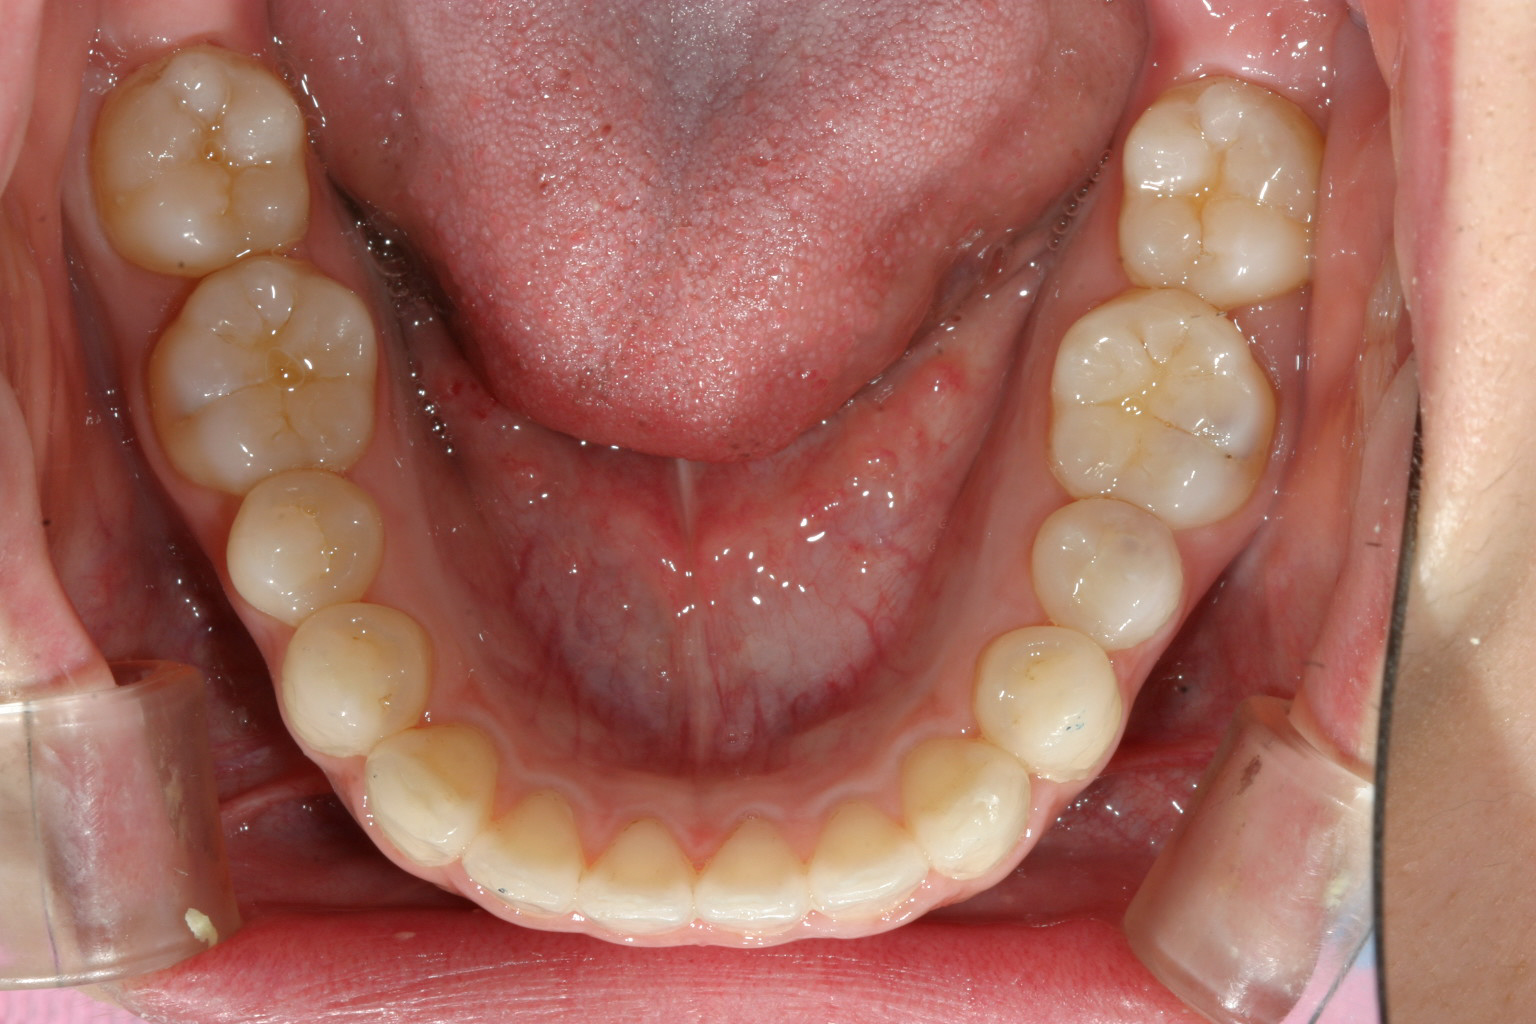

下顎はアーチを広げました。

上の写真と比較してください。 かなり引っ込みました。

V字型のアーチをU字に改善するのと小臼歯抜歯する事でインビザラインで最大限に引き込めました。

かなり綺麗に仕上がったと思います。